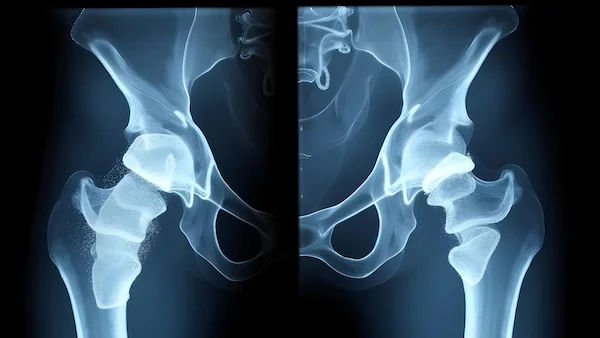

Why Is Positioning Important After Hip Replacement?

After hip replacement surgery, your new joint needs time to heal and stabilise. Certain movements or positions can put stress on the hip, increasing the risk of dislocation (when the ball of the joint comes out of the socket). To prevent this, doctors recommend specific guidelines on how to sit, stand, lie down, and move during recovery.